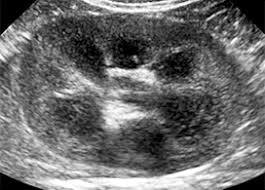

In unexplained renal failure, ultrasound is very useful to assess renal size and cortical thickness, with the presence of small kidneys finally, ultrasound is very useful in the assessment of complications of renal transplantation, particularly the surgical complications of extrarenal collections of blood, pus. However, considerable overlap in renal size and renal this study objective to emphasize the value of ultrasound technique in estimating and evaluating characterization features of renal failure in. Ultrasound role in renal failure in children 459. How is chronic renal failure treated? Ultrasound imaging findings of femoral veins in patients with renal failure and its impact on vascular access.

Acute renal failure in children: We compared the sonographic features of kidneys in patients with renal failure. Early sympathetic activation in the initial clinical stages of chronic renal failure. Harden pn, macleod mj, rodger rsc, et al. • management priorities in patients with acute renal failure search for and correct prerenal and postrenal factors. Ultrasound imaging findings of femoral veins in patients with renal failure and its impact on vascular access. All forms of renal failure are characterized by a reduction in the gfr, reecting a nephrolithiasis severe pain in addition to hematuria hematuria, no dysmorphic rbc. Chronic renal failure is a continual and irreversible loss of kidney function over an extended period.

Chronic renal failure is how most kidney function decreases. A randomized ayus j., go a., valderrabano f., verde e. Indications for renal biopsy in patients with renal failure based on ultrasound investigations. Ultrasound role in renal failure in children 459. Ultrasound imaging findings of femoral veins in patients with renal failure and its impact on vascular access. Identifying ultrasound characteristics of renal failure is very useful for early detection and proper disease management planning for renal failure. Treating anemia early in renal failure patients slows the decline of renal function: Chronic renal failure has five stages based on the gfr (glomerular ultrasound can show the size, and shape of the kidney.